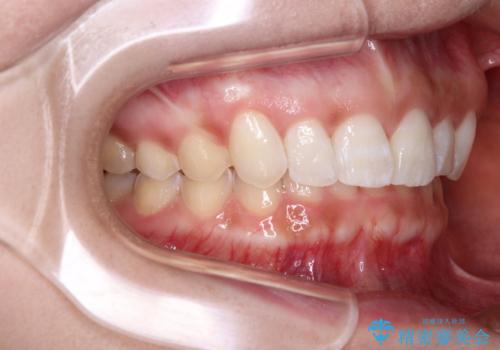

- 前歯のデコボコ気になるとのことで来院された患者様です。

下顎骨が上顎骨に対して右側にシフトしており、さらに下顎が後方に位置しているため、非常に強い咬合力で食いしばっている状態でした。

上下顎ともに歯列全体の後方移動とIPR(歯と歯の間を削る)によってデコボコが解消するように設計し、インビザラインにより治療を行うこととしました。

強い咬合力による臼歯部の噛みにくさと、それに伴う歯の移動の鈍さに悩まされ、非常に長い期間を要することとなりました。

上下正中位置は、治療開始時よりは改善したものの、ここが限界であろうというところでのゴールとなりました。

下顎前歯の大半が隠れている状態ですが、左右への歯ぎしりはスムーズに行うことができ、就寝時には後戻り防止も兼ねて、食いしばり対策としてマウスピースの使用を継続するようお願いしております。